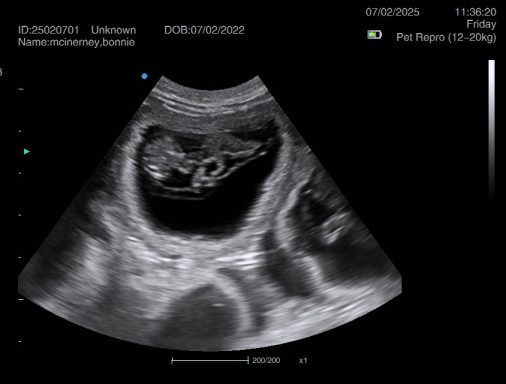

Ultrasound pregnancy scanning is a safe, non-invasive way to confirm pregnancy in dogs and cats, offering breeders and pet owners peace of mind and vital information to support responsible care. It allows us to detect gestational sacs, assess foetal development, and estimate litter size—all while ensuring the wellbeing of the animal.

Pregnancy can sometimes be detected as early as Day 18 post-mating, but scanning at this stage is not routinely recommended. Embryos are still developing and may not be clearly visible, and there is a natural risk of embryo resorption, which can lead to misleading or inconclusive results.

For the most accurate and reliable scan, we advise booking between Day 25 and Day 32, when pregnancy is more easily confirmed and foetal structures are clearer. If an early scan is performed and no pregnancy is detected, we offer a FREE complimentary re-scan after 7 days at the clinic to ensure clarity and support informed decision-making.

Our approach balances early insight with ethical care—always prioritizing the comfort of the animal and the accuracy of the results.

Gallery